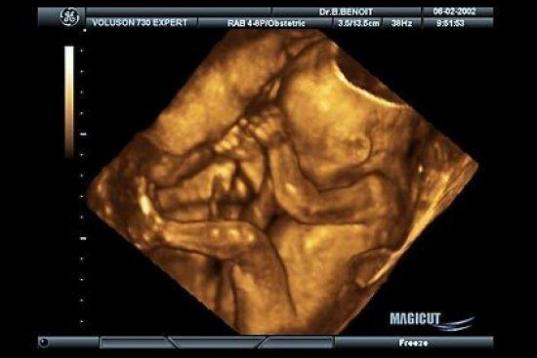

En esta galería puedes ver en fotos como es el desarrollo de un feto de semana en semana:

Desarrollo del feto, en fotos